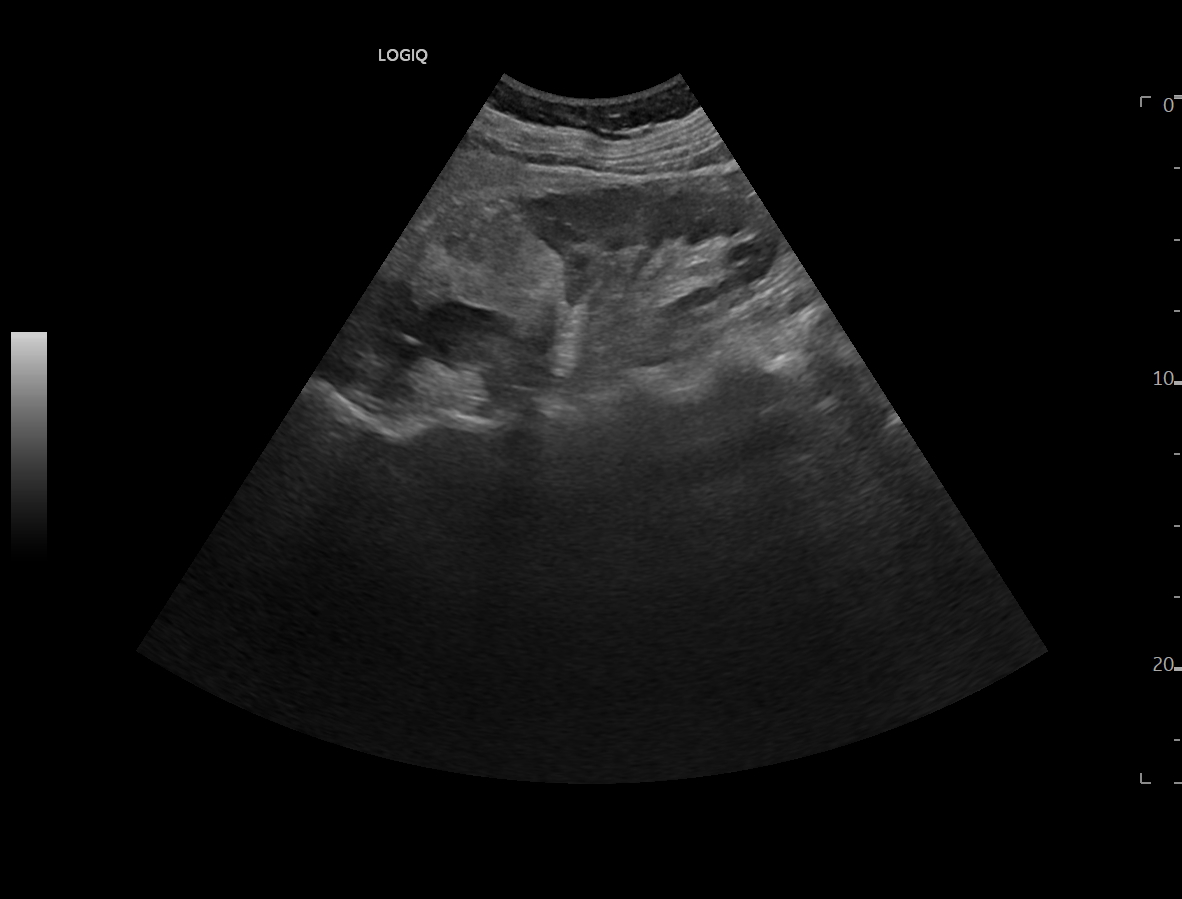

Se realiza ecografía clínica objetivando esteatosis hepática así como litiasis en vesícula biliar que mide 1,6 cm sin signos de complicación. A nivel del riñón derecho presenta lesión hiperdensa en zona media y polo inferior que no capta con realce, sin apreciarse dilatación de cáliz. Se consulta con radiólogo de guardia que indica realizar TAC abdominal para filiar.